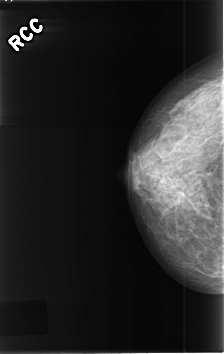

C_0461_1.RIGHT_CC

RIGHT_CC LINES 4592 PIXELS_PER_LINE 2904 BITS_PER_PIXEL 12 RESOLUTION 50 NON_OVERLAY